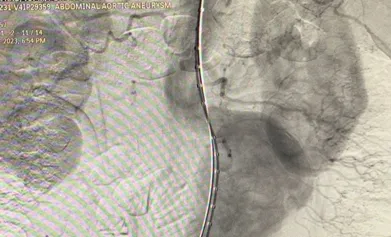

The Abdominal Aortic Aneurysm (AAA) was extending from the infra-renal aorta to both Common iliac arteries. Endovascular Aneurysm Repair (EVAR) was planned. Generally, an EVAR is done by surgically exposing femoral arteries bilaterally to take the grafts inside the aorta for Endovascular repair. We did the EVAR completely percutaneous- avoiding any surgical exposure. No Groin Cut, No surgical femoral artery exposure # SIMPLY Percutaneous. The patient Got discharged in 48 Hrs. It’s actually technically challenging to create 2 X two sets of pre-close sutures / Bilateral femoral for 20F (6mm) holes on Common femoral arteries. The procedure was done with suture closure of Bilateral 6 mm holes over the femoral without exposing the femoral - that’s the beauty.

suture-less-endovascular-aneurysm-repair-for-abdominal-aortic-aneurysm-3